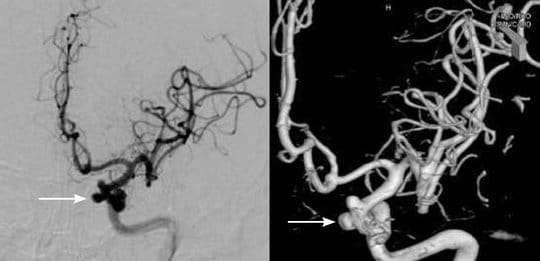

3.検査中に脳動脈瘤が再破裂したり、脳内出血を起こしたりすることが稀にあります。